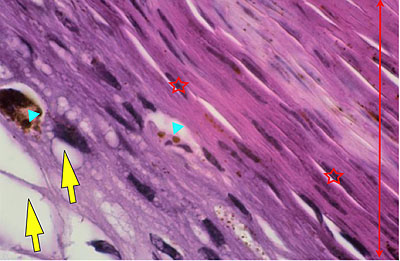

Photo 3 (Hémalun Eosine X 100) : aspect bleu-blanc-rouge à plus fort grossissement,

bleu pour hyperplasie des couches basales, blanc pour vacuolisation des acanthocytes

sous-cornés et rouge pour parakératose de la couche cornée. Le derme superficial est

le siège d’un infiltrat inflammatoire mononucléé périvasculaire modéré.

Légendes de la Photo 3 :

- Flèche bleue pour hyperplasie des couches basales

- Flèche blanche pour vacuolisation des acanthocytes sous-cornés

- Flèche rouge pour parakératose de la couche cornée

- Étoile rouge : Le derme est faiblement à modérément inflammatoire

Photo 4 (Hémalun Eosine X 100) : aspect bleu de l’épiderme pour hyperplasie des couches basales, qui dessinent des crêtes épithéliales allongées, filiformes, ramifiées et branchues, peuplées de cellules basales hyperbasophiles. L’épiderme est multifocalement exulcéré. L’infundibulum folliculaire visible présente une hyperkératose parakératosique sans visualisation nette d’une couche des grains. Le derme montre une discrète angiectasie des capillaires du plexus superficial ainsi qu’un discret infiltrat inflammatoire périvasculaire superficial.

Légendes de la Photo 4 :

- Triangles bleus foncés : contours de crêtes épithéliales allongées, filiformes, ramifiées et branchues, peuplées de cellules basales hyperbasophiles.

- Triangles bleus clairs : exulcération épidermique

- Flèche rouge : parakératose épidermique et folliculaire

- Étoile rouge pleine :Le derme est faiblement à modérément inflammatoire (infiltrat mononucléé)

- Étoile rouge creuse : angiectasie des capillaires sanguins

- Étoile bleue claire : glandes sébacées